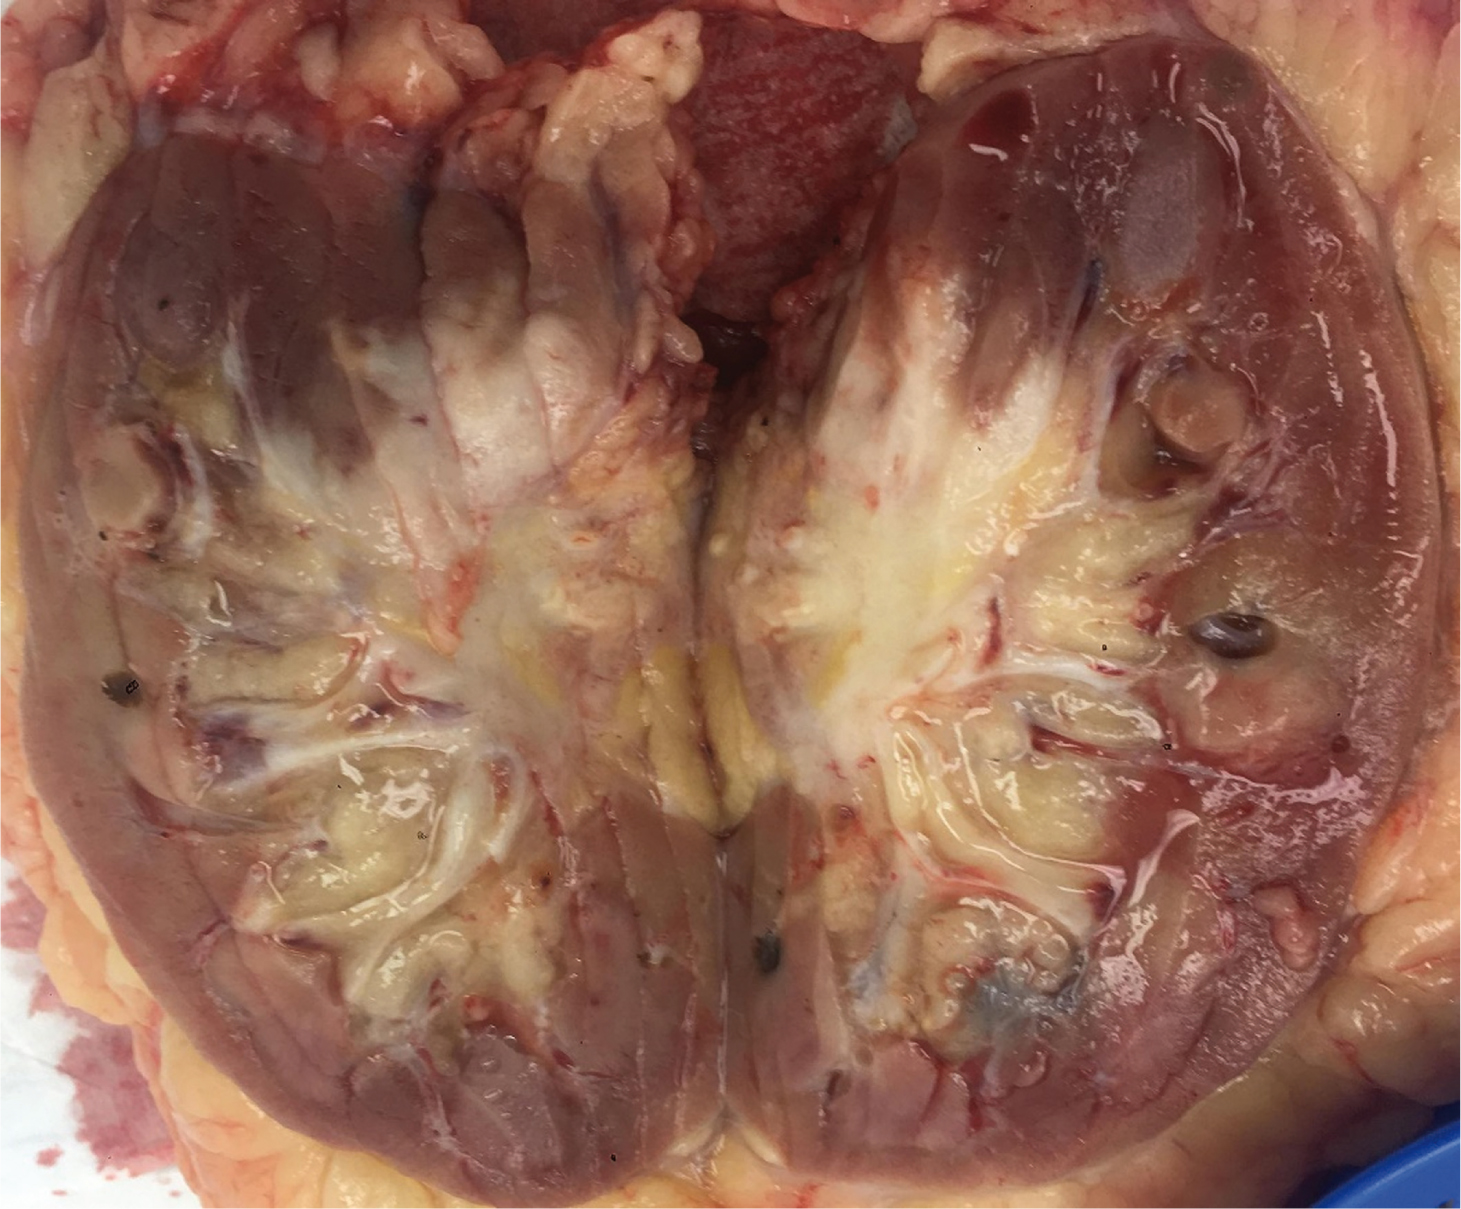

Macroscopic features showed a 45 mm cream-coloured tumour in the mid- to upper pole with no haemorrhage or necrosis (Figure 2). The tumour showed invasion through the IVC wall, extending into the psoas muscle. Histopathology demonstrated a moderately differentiated SCC with associated fibrosis (Figure 3). The tumour also showed extensive lymphovascular invasion and peri-neural invasion involving the vascular margin. Two of the five resected hilar lymph nodes demonstrated involvement, whereas the one resected pre-aortic lymph node did not demonstrate involvement. The patient was referred to a radiation oncologist to discuss the possibility of adjuvant radiotherapy.

Fig 3

Figure 3. Histopathology from tumour specimen demonstrating a moderately differentiated squamous cell carcinoma with associated fibrosis H&E × 200.